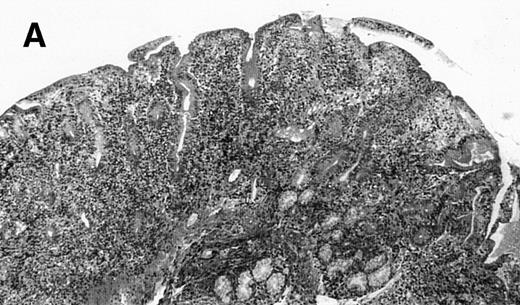

The 4 patients with complicated CD had duodenal biopsies consistent with untreated CD; total villous atrophy, intraepithelial lymphocytosis, crypt hypertrophy, and inflammation of lamina propria with benign-appearing lymphocytes, plasma cells, and eosinophils were observed. There was no histological evidence of lymphoma. Patient no. 4 also had biopsies performed at the border of duodenal ulcerations that showed epithelial erosions without histological evidence of lymphoma.

(A) Case no. 1. (B and C) Case no. 2. (D) Case no. 3. (E) Case no. 4. (A, B, D, and E) Duodenal biopsies showing total villous atrophy with crypt hyperplasia and infiltration of lamina propria by nonatypical inflammatory cells (Hematoxylinandeosin; original magnification × 10). (C) Jejunal biopsy showing villous atrophy and ulcerations with regenerative epithelial changes on the border of ulcerations; no evidence of lymphoma.